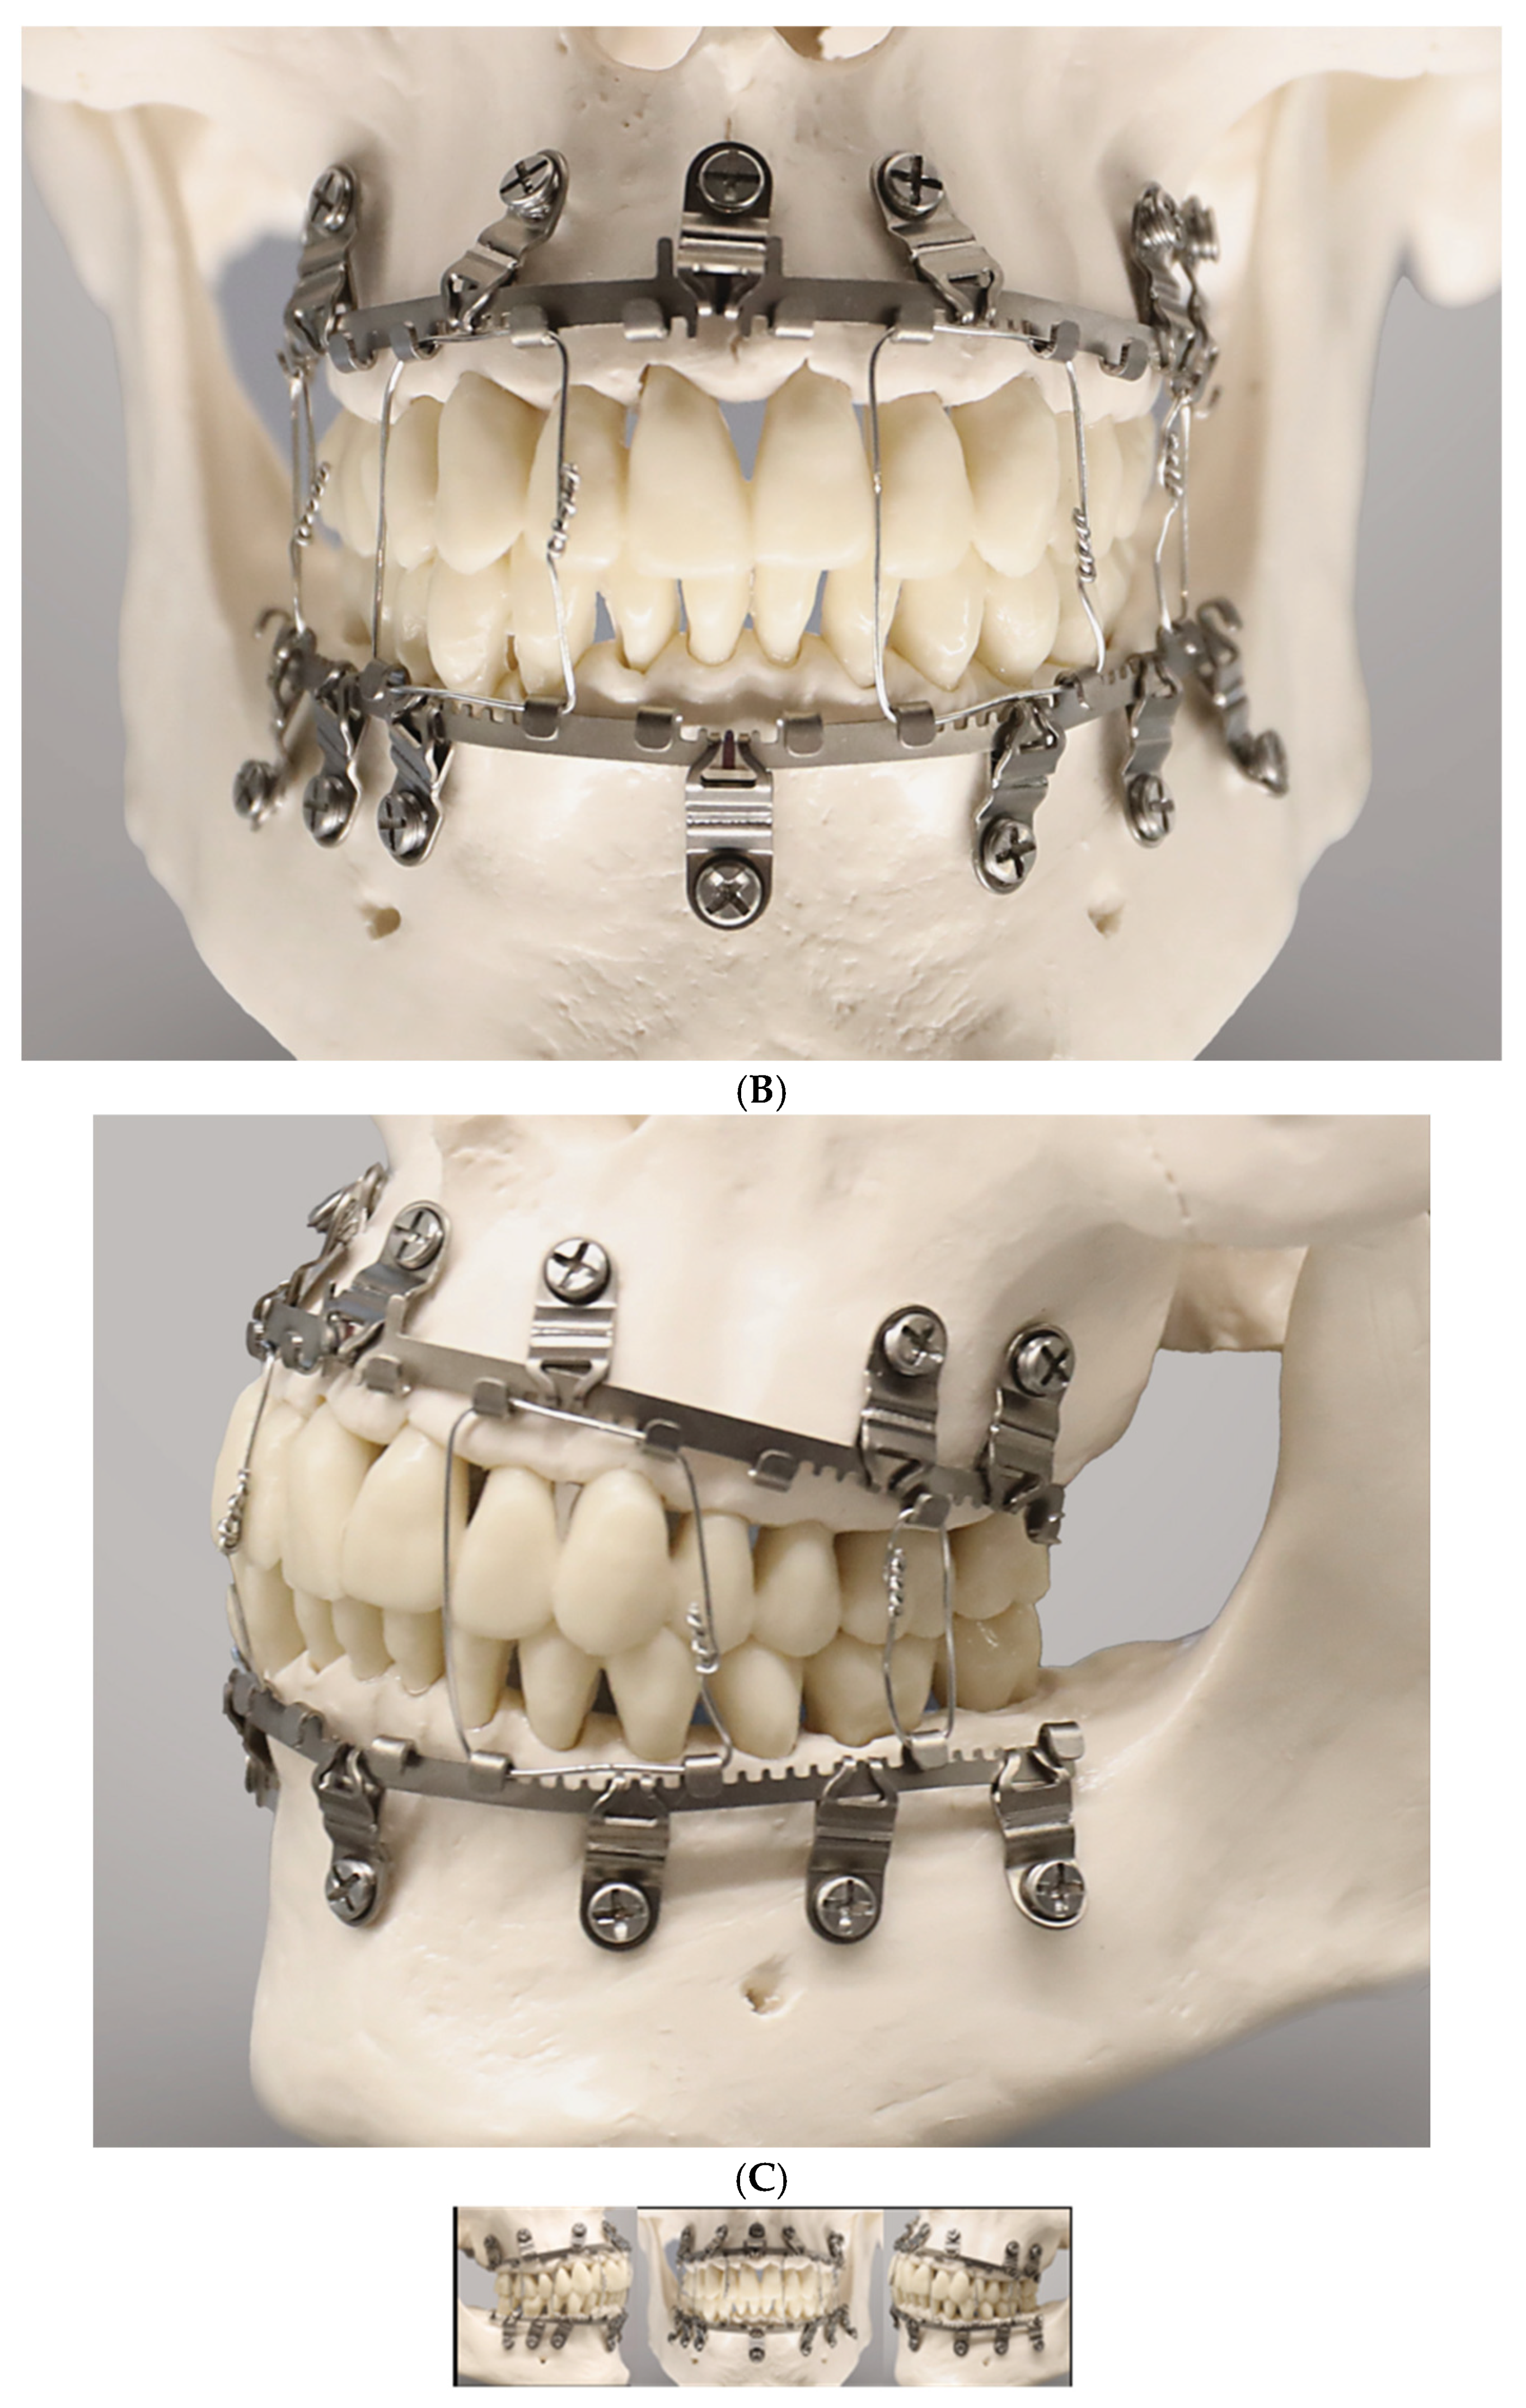

Figure 5.

(A) Full arch assembly of L1 MMF arch bar/slider plates and intermaxillary wire ligatures in a model—right lateral view. The maxillary bar sections above the incisors and premolars as well as the mandibular bar sections below the lower lateral incisors are void of tabs and gaps (‘teeth’); the angulation of the lateral slider plates and montage under tension maintains the purposed interdigitation between their slots and the arch bar rack. Note: suboptimal asymmetrical vertical placement of lower lateral arch bar sections subsequent to in plane bending alongside the free gingival margins and tooth necks (periodontally unfavorable). (B)—frontal view. Angulation of slider plates in upper incisor/canine regions; apart from a midline slider plate the lower incisor and canine region are spared from slider plates accounting for the high risk of tooth root injuries due to narrow interradicular spaces. (C)—left lateral view. The slider plate below the lower canine is not properly engaged in the mating bar rack resulting from a too parallel montage—a flaw—in long-term yielding to forces and potentially hazarding stability. Source/origin: L1 MMF System provided by courtesy of KLS Martin, Tuttlingen, Germany—model montage by C.P. Cornelius.